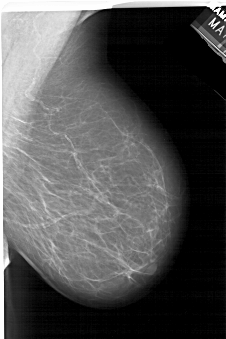

A_1464_1.LEFT_CC

LEFT_CC LINES 6646 PIXELS_PER_LINE 3751 BITS_PER_PIXEL 12 RESOLUTION 43.5 NON_OVERLAY